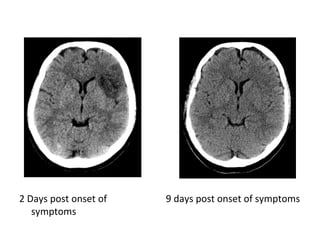

2 Days post onset of

symptoms

9 days post onset of symptoms